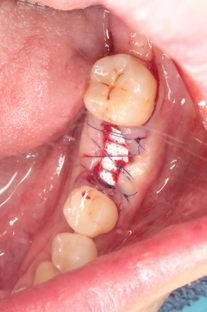

処置自体は抜歯と同日に行えることが多く、骨補填材を抜歯窩に填入した後、コラーゲンメンブレンや縫合で保護するという内容です。処置後は数ヶ月かけて材料が自分の骨へと置き換わっていき、顎の形態が安定します。

32歳女性